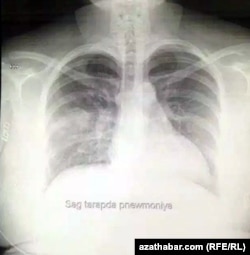

Aşgabatda COVID-19 hassasynyň öýkeniniň rentgen suraty

Şeýle-de Azatlyk Radiosynyň redaksiýasyna COVID-19 hassasynyň rentgenden geçen suraty gelip gowuşdy.